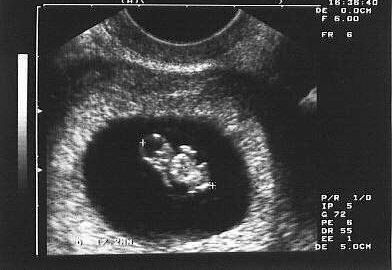

Early Sonography

Before 10 weeks

For this, Sonography is done vaginally (internal examination).